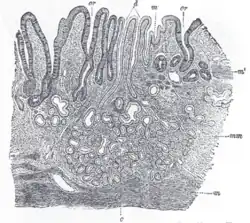

Stavba stěny žaludku

Sliznice žaludku je silná, tmavě růžová, v prázdném žaludku složena v nepravidelné řasy, mezi řasami ústí žlázy žaludečních šťáv. Je krytá jednovrstvým epitelem, na povrchu je vrstva hlenu, která chrání před natrávením. Podslizniční vazivo je spíše řídké s elastickými vlákny, tukovými buňkami, cévními a nervovými pletenci. Mimoto je ve stěně také hladká svalovina, která je nejsilnější v pyloru.

Žaludeční stěna se tedy skládá ze čtyř částí:

- sliznice – s množstvím žaludečních žlázek

- podslizniční vazivo

- svalová vrstva

- serózní povlak

Sliznice žaludku

Sliznice žaludku je u živého člověka oranžově červená, u mrtvého pak bledá a natrávená. Na jejím povrchu se nachází ochranný hlen. Na sliznici rozlišujeme řasy sliznice (plicae gastricae), podélné řasy a Waldeyrovu cestu (sulcus salivarius). Její povrch se člení na:

- žaludeční políčka (areae gastricae) – políčka o rozměru 2–6 mm oddělená vkleslinami

- žaludeční jamky (foveolae gastricae) – hluboké krypty vystlané povrchovým epitelem sliznice, do jejich dna ústí žaludeční žlázy (2-7 ks)

- žaludeční žlázy (glandulae gastricae) – kolmé k povrchu sliznice, od dna jamek formou tubulózních žláz do slizničního vaziva až k lamina muscularis mucosae